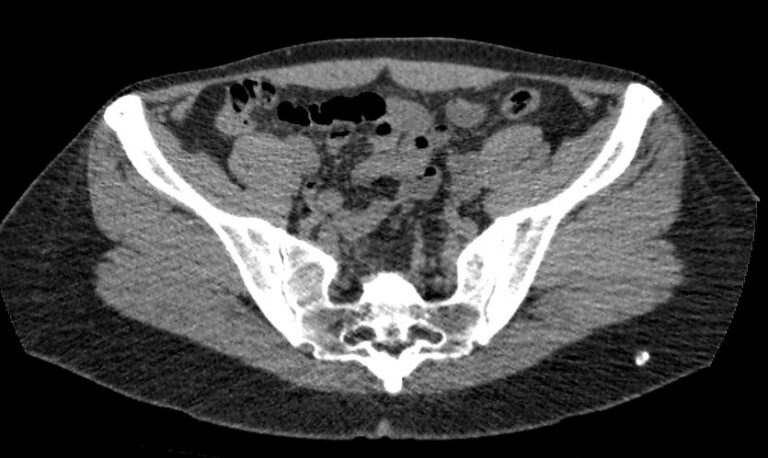

Методика КТ позволяет оценить анатомическое строение почек, надпочечников, состояние мочеточников и мочевого пузыря, кроме того, дает возможность визуализировать сосудистую систему и регионарные лимфатические узлы.

Сканирование применяется для выявления воспалительных заболеваний почек, чашечно-лоханочной системы, мочеточников и мочевого пузыря, также позволяет обнаружить конкременты на фоне мочекаменной болезни, диагностировать доброкачественные и злокачественные новообразования, точно классифицировать кистозные образования по системе Bosniak, что особенно важно для урологов и нефрологов, а также определить степень поражения регионарных лимфатических узлов. Кроме того, КТ используется для диагностики травматических повреждений органов мочевыделения, аномалий развития почечно-лоханочной системы, дает максимальную информацию для хирурга при планировании оперативного вмешательства.

Что показывает КТ почек, мочеточников, мочевого пузыря

- опущение почек;

- аномалии развития почек, мочетоников

- доброкачественные и злокачественные новообразования;

- камни (конкременты);

- уретероцеле

- сосудистую патологию (сосудисто-мочеточниковый конфликт, инфаркт почки);

- последствия оперативных вмешательств;

- увеличение лимфоузлов в брюшной полости, забрюшинном пространстве и малом тазу;

- травматические изменения

- патологии сосудов малого таза.